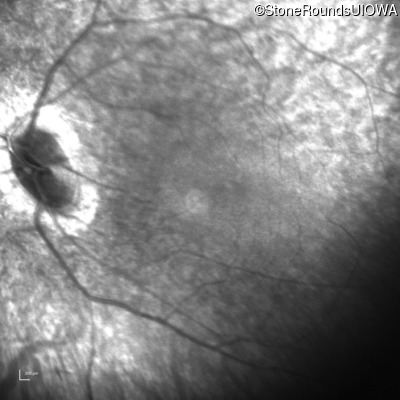

Age at visit:

28 years

OD

OS

Light Perception

OCT Stack

SECORD

RPGRIP1

His631Arg CAC>CGC

Pro237 del1ccA

AR